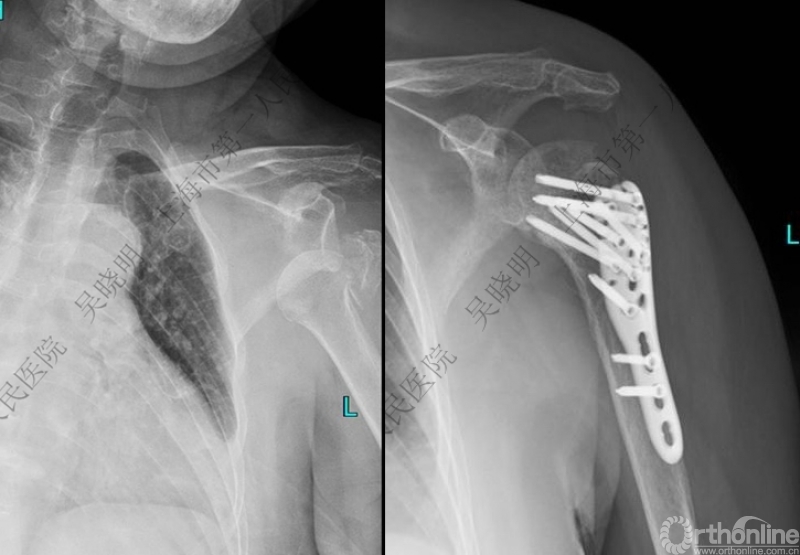

外翻压缩型肱骨近端骨折

钢板固定

X线是孤立性向下移位的大结节,一定要小心,多伴有肱骨外科颈骨折

全麻下闭合复位,钢板固定